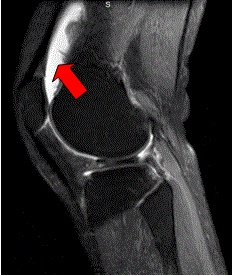

膝关节“积水”,即膝关节积液。当膝关节滑膜与周围组织出现炎症反应,滑膜分泌的滑液量增加,滑膜表面正常吸收和分泌功能失衡,滑液无法及时吸收,在关节腔内积聚形成关节积液。

膝关节肿胀:通常是最明显的表现,当膝关节积液过多时,髌骨囊出现明显肿胀,可看到皮肤表面有隆起,按压髌骨可感受关节内有液体流动。